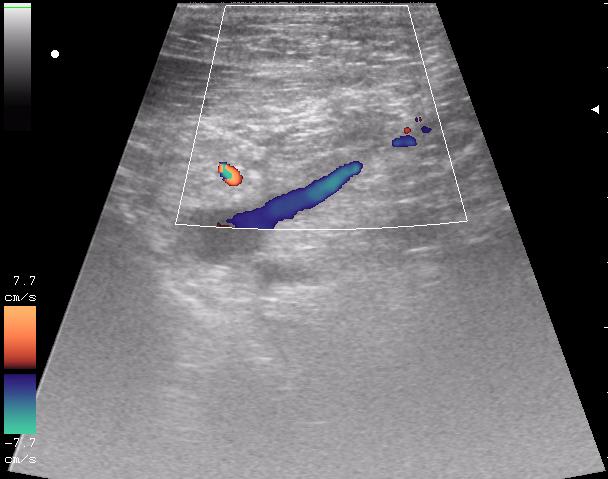

и в отношении второго снимка: там какой именно сосудистый пучок? - и что именно исключали этим сканом

исключали повреждение отломками подключичную артерию и вену ( был огроменный отек)

кстати, вот вена